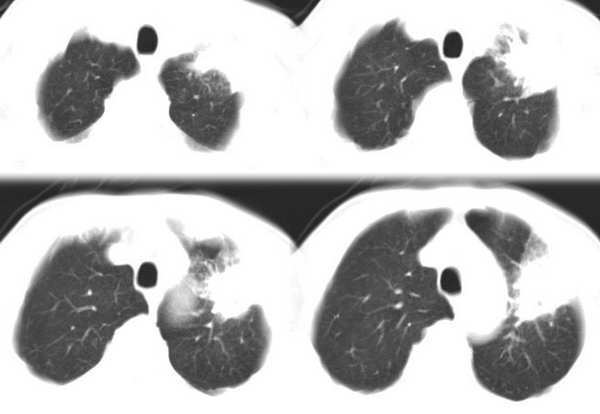

左肺上叶胸膜下不规则团块阴影,内见空泡,边缘光整,肺纵比率>50%,支持左肺癌的诊断。

ct:左上肺块状影、其内徐点状气体外蜜度大致均匀。周围粗大索状影

其内透光影仔细观察像是支气管,病灶周围有渗出改变,该病灶不考虑感染性病变,机化性肺炎能排除吗

理由:1 病灶有恶性肿瘤的特征:空泡征,毛刺,棘状突起

左上肺病灶与胸膜脂肪线存在,未见明显胸膜凹陷征,虽然病灶边缘不规则,但未见明显“短毛剌、切迹征、免耳征、血管束集征”,其间亦见条索状、斑点状影,认为左上肺结核或炎性病变>周围型肺癌。

病灶比较虚 周围有明显渗出 卫星灶及条素影 病灶边缘有棘突 胸膜外脂肪层存在考虑结核

考虑肺结核可能性大。理由1.病灶形态不规则,其周有卫星灶,2.病灶没有毛刺征,灶周出现粗大索条影.